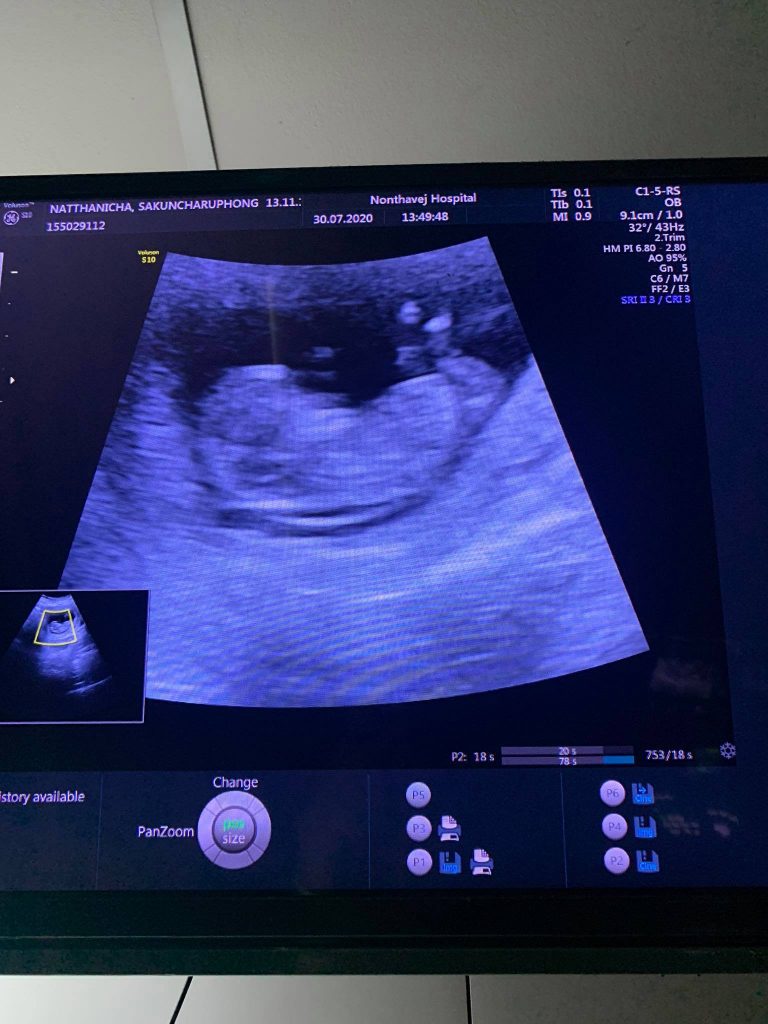

นิกกี้ พริตตี้เงินล้าน ท้องลูกคนที่ 2 โดยเธอและสามีอาจารย์เฟียร์กำลังลุ้นกันอยู่ว่าจะได้ลูกชายหรือลูกสาว ล่าสุดนิกกี้ได้ไปฝากท้องแล้วที่ รพ. คุณหมอบอกว่าตอนนี้ท้องได้ 3 เดือน และอีก 1 เดือนก็จะรู้ว่าน้องจะเป็นผู้หญิง หรือผู้ชาย